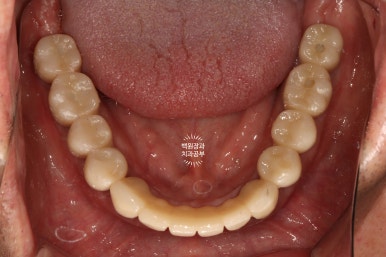

구강내 교합면 사진입니다.

모든 치아가 지르코니아 크라운으로 제작되어, 진짜 자연치같은 형태를 재현해내고 있습니다.

지르코니아 크라운운 캐드캠으로 제작되기 때문에 상당히 자연치와 유사한 형태와 색감을 냅니다.

임상적으로 아주 만족스러운 결과네요.